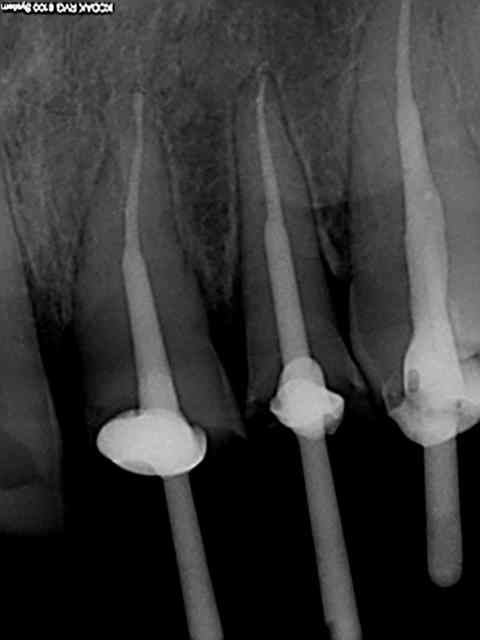

R1 jf6pzt - Eugenol

R2 k7cybs - Eugenol

R3 i3jjn6 - Eugenol

R4 dveqiy - Eugenol

Zoom incisives eb4rim - Eugenol

Retraitement et cour prov ej8sen - Eugenol

Canaux calcifi s e685ou - Eugenol

Avec provisoires o4ho8c - Eugenol

Lol ! je vois qu'on a la meme technique. c'est pas du no post no crown, mais je sais faire ca aussi. ))))))

Sur les monoradiculées, les tenons sont un peu trop courts. Avec les années, si l'os alvéolaire diminue, les risques de fractures de racines augmentent lorsque le bout du tenon se retrouve au niveau du rebord alvéolaire.

je fait extrêmement peu de tenon, mais tu nous présentes un travail soigné au moins d'un point de vue radiologique, sur la technique endo intrinsèque je laisse le soin a chacun de se faire une opinion